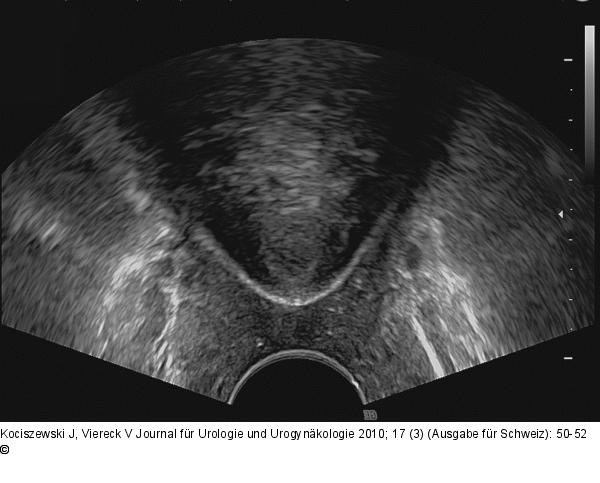

Abbildung 2: TVT-Band

Sonographisches Bild bei korrekter Bandlage in Horizontalebene. |